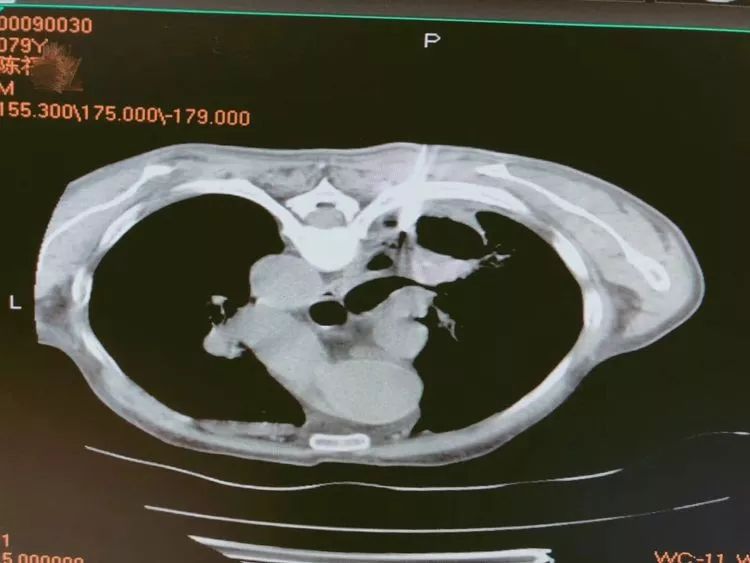

第一例 79岁的陈爷爷来省胸科医院就诊,经检查胸部CT厚壁空洞,气管镜检查提示外压性狭窄,为明确诊断,肺穿刺是最佳选择,通过CT引导,洞壁取材。

从影像学上考虑肿瘤的可能性更大,一般空洞我们多考虑鳞癌,可是,病理报告告诉我们,腺癌也可以形成大空洞,同时患者椎体MRI提示骨转移,错失最佳治疗时机。